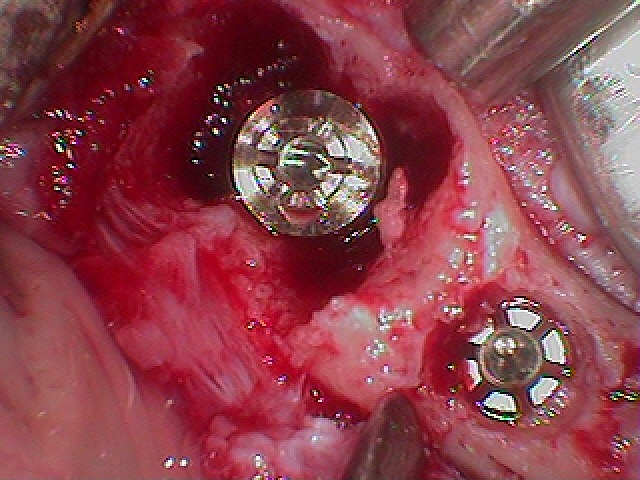

即時インプラント埋入を行っています